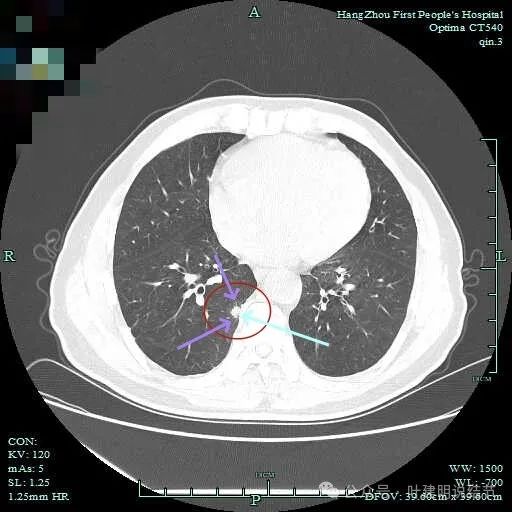

先看主病灶情况:

病灶出现,整体轮廓较清,胸膜略有牵拉。

密度不均匀,胸膜有轻微牵拉,边上有磨玻璃成分。

混合偏实性密度,瘤肺边界清,胸膜有牵拉。

表面不平,有小血管进入,整体轮廓与边界清。

明显胸膜牵拉以及血管进入,灶内密度不纯。

边缘毛糙有细毛刺,灶内密度不均;胸膜牵拉以及表面不平;黄色箭头示细支气管截断的样子。

血管征以及胸膜凹陷征。

轮廓与边界清,灶内有小空泡征。

多支血管进入,灶内密度不均。

胸膜牵拉,表面不平,血管进入并有异常增粗。

此层见血管穿行,但整体显散。

边缘区轮廓稍显不清。